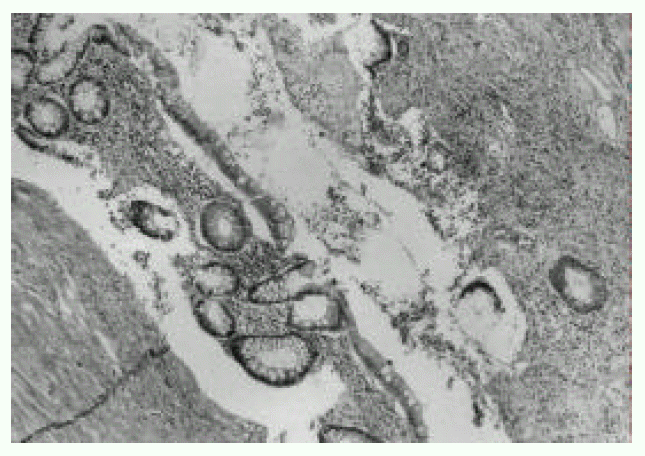

Figure 4.

Photomicrograph showing fistulous track partly lined by the colonic epithelial tissue (H&E stain, original magnification × 40).